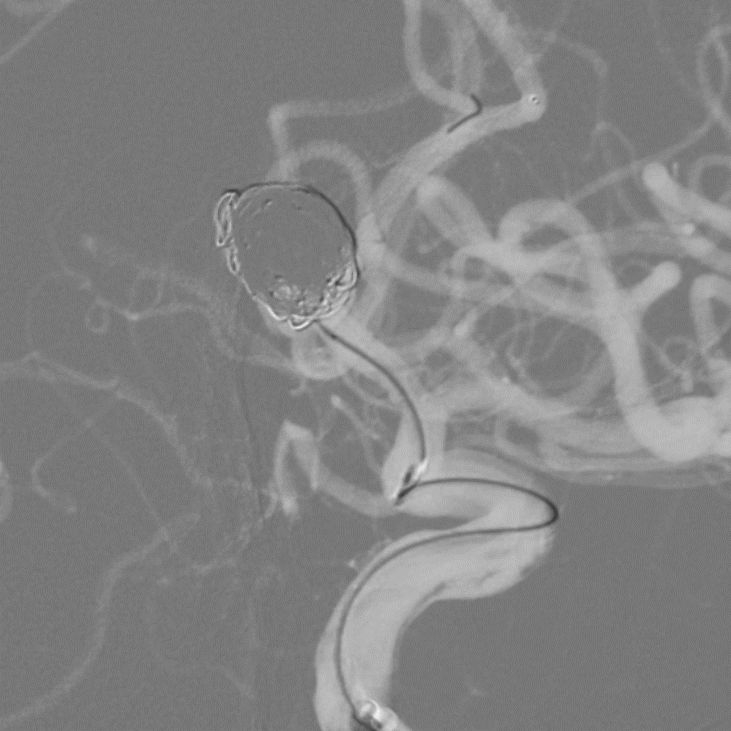

➢术后造影

载瘤动脉通畅,右侧颈内动脉造影见右侧大脑前动脉A1、A2开放良好;

➢术后3D重建

术后3D重建